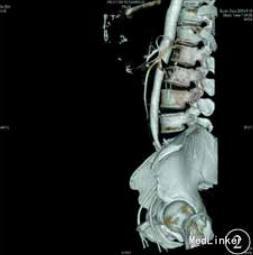

体查:振水音阳性,行胃肠减压引流胃液及胆汁>1000 mL/d。腹部立位X线片未见异常。复查增强 CT和腹部血管造影示:十二指肠水平部狭窄伴前方肠系膜血管压迫,考虑肠系膜血管压迫综合征。

予加强静脉营养、内科保守治疗,无好转,再行上消化道碘油造影示十二指肠水平部狭窄,造影剂无法通过,采取俯卧位后造影剂可通过,但十二指肠升部与空肠交界处狭窄,造影剂无法通过。考虑存在十二指肠与空肠交界处病变,恶性肿瘤不能排除,遂决定手术探查。术中在十二指肠升部与空肠交界处可见一肿瘤,最大径约为3cm,累及浆膜,相应肠管狭窄梗阻,系膜可见肿大淋巴结,另可见肠系膜上血管与腹主动脉间脂肪组织减少,十二指肠水平部部分被压迫,探查其余小肠及结肠未见异常,肝脏、盆腔、腹主动脉旁未见明显转移,腹腔未见腹水。术后病理诊断示小肠中至低分化腺癌,侵及浆膜外脂肪组织,脉管中见癌栓。上、下切端均未见癌组织累及,周围脂肪组织中的16枚淋巴结中5枚见转移性癌组织,另见癌结节2枚。免疫组织化学检查示,细胞角蛋白7阴性,细胞角蛋白20、CEA 、绒毛蛋白、细胞角蛋白19、CA19-9和 CD34血管阳性,Ki‐67抗原约85%阳性。术后患者恢复良好,无恶心、呕吐,出院后胃纳正常。1个月后复诊体质量增加约5 kg。